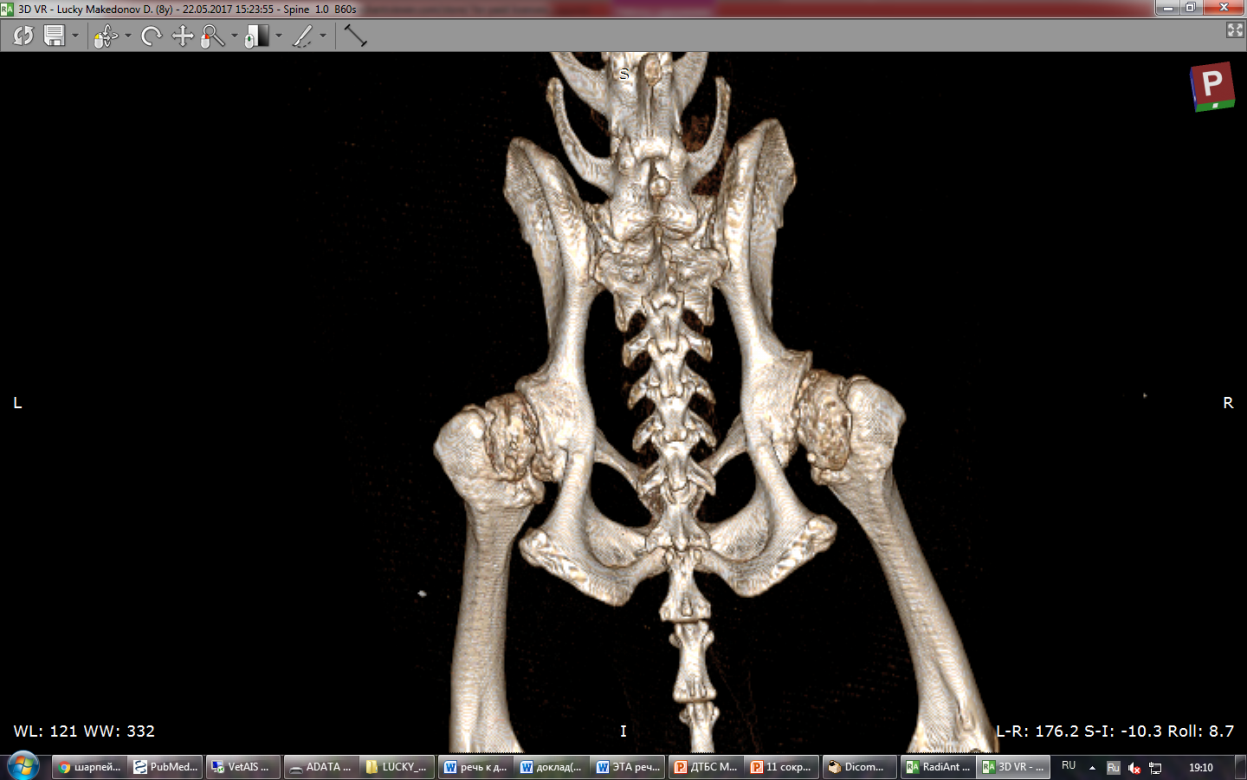

КТ таза, билатеральный коксартроз немецкой овчарки вследствие дисплазии